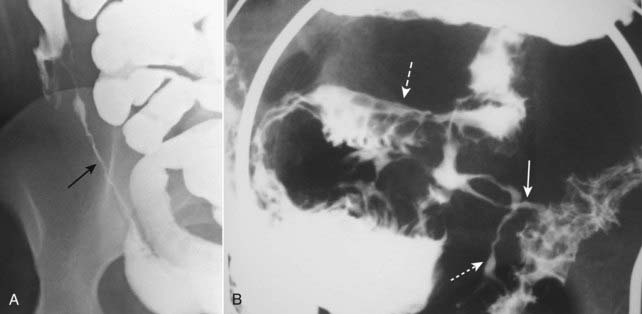

image

Figure 18-12 Crohn disease.

A, The terminal ileum (solid black arrow) is markedly narrowed (string sign) and stands apart from other loops of small bowel (proud loop). B, A close-up image of the right lower quadrant from a small bowel follow-through study in another patient shows multiple streaks of barium (solid and dotted white arrows) representing multiple enteric fistulae originating from an abnormal loop of small bowel (dashed white arrow) and connecting with each other and the large bowel. Fistula formation is a common complication of this disease.